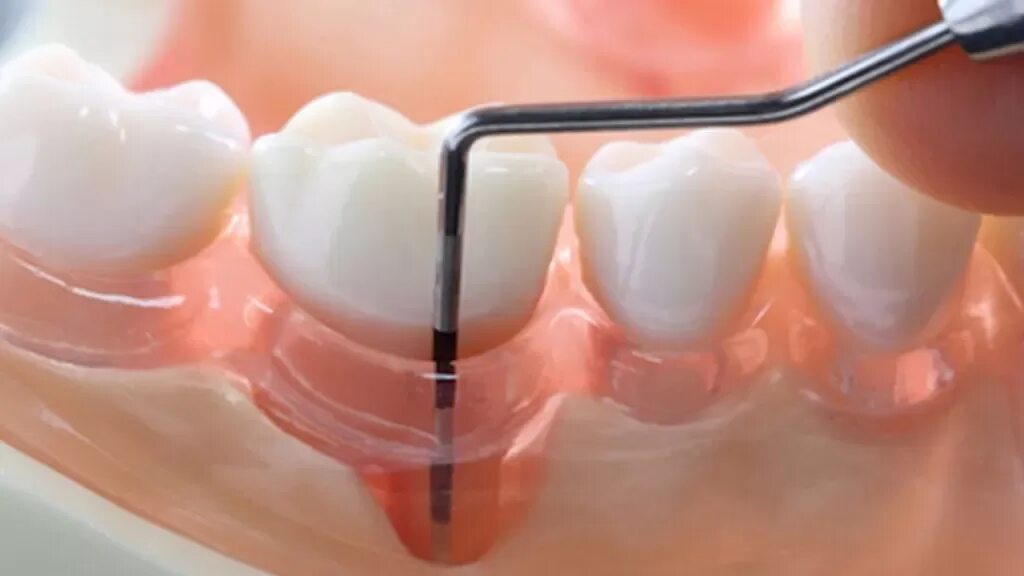

Зубной карман